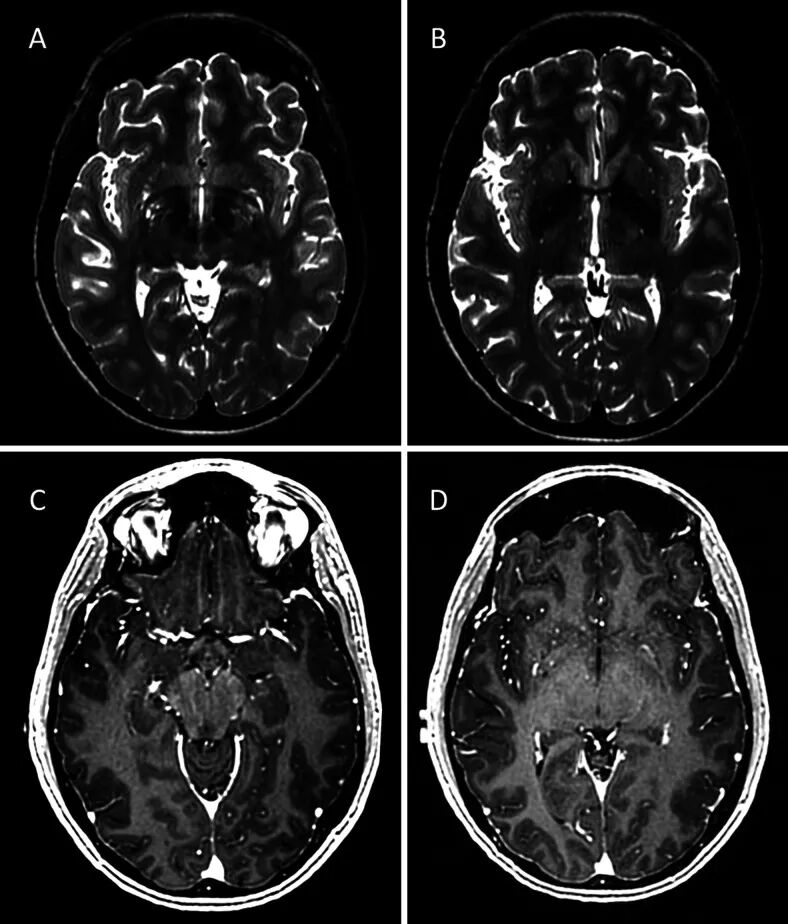

病例一:37岁女性患者,以新发左侧头痛为主要症状,外院影像学检查提示左额颞叶新发占位性病变。神经系统检查未见异常表现。头颅MRI检查显示左侧岛叶IV区局灶性高信号影,T1增强扫描显示左侧大脑中动脉分支周围血管周围强化。初次影像学评估符合低级别胶质瘤表现。

在计划手术干预前7周进行的复查影像学检查显示,T2、FLAIR及T1增强序列上的岛叶IV区病灶已完全消退,左侧大脑中动脉周围强化现象消失。值得注意的是,患者在复查前未使用类固醇药物治疗。

病例二:41岁女性患者,有偏头痛病史,因头痛性质改变就诊。神经系统检查无异常发现。头颅MRI显示左侧岛叶IV区局灶性高信号,伴大脑中动脉分支周围血管周围强化。初步诊断考虑岛叶低级别胶质瘤。

6周后复查MRI显示,左侧大脑中动脉强化和岛叶病灶均已完全消退。11个月后随访影像显示病灶消退状态稳定。该病例同样未使用类固醇治疗,未进行脑脊液检查。